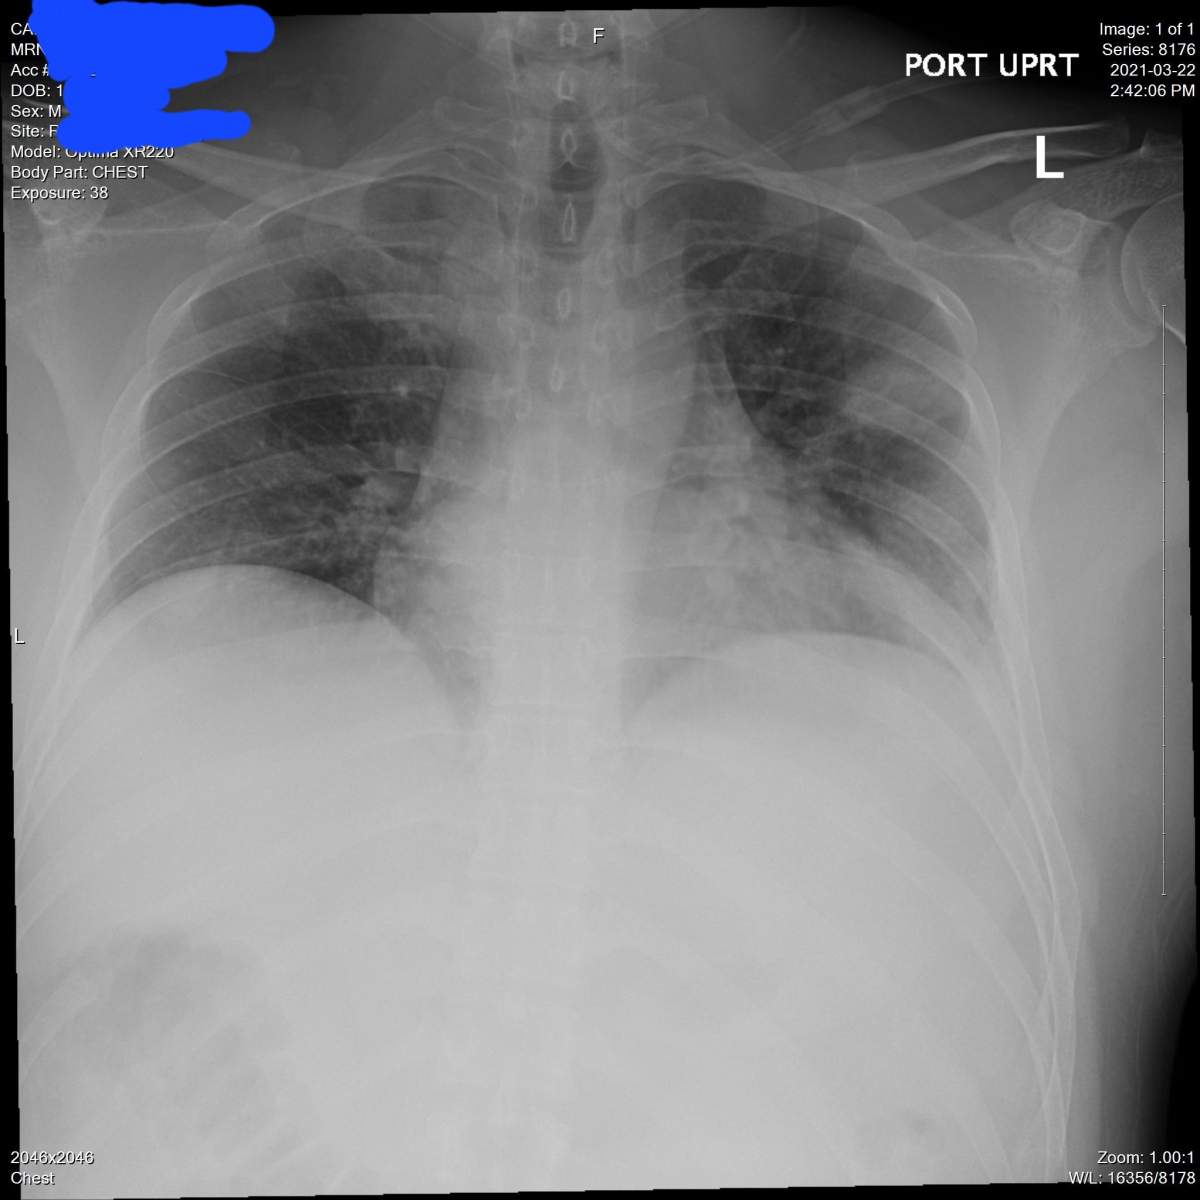

Cardinal tested positive for COVID-19 on March 19, 2021. His health deteriorated rapidly soon after his diagnosis, leading to him calling 911 on March 22 when he experienced shortness of breath, constant hiccups and what felt like phlegm in his lungs.

This X-ray image of Matthew Cardinal’s lungs was captured on March 22, 2021. Courtesy: Matthew Cardinal

In an effort to show the public what it looks like to suffer from long COVID symptoms, Cardinal recently shared X-ray images of his lungs on his social media.

“I’m showing what a serious COVID-19 infection looks like. These are my X-rays,” he captioned one of his posts on Twitter.